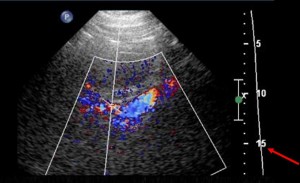

Renal artery ultrasound

Excellent image of renal artery ultrasound from the midline